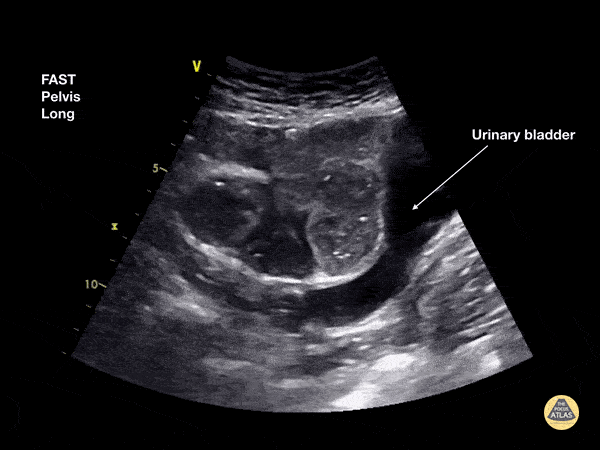

65 female patient 6 months post bowel resection (lower midline laparotomy scar) presents with vague abdominal pain. She is maximally tender over the scar. Bedside ultrasound shows dilated bowel loops and 'to and fro' peristaltic movements. CT confirmed small bowel obstruction and her care was expedited Dr Cian McDermott, Mater University Hospital, Dublin, Ireland